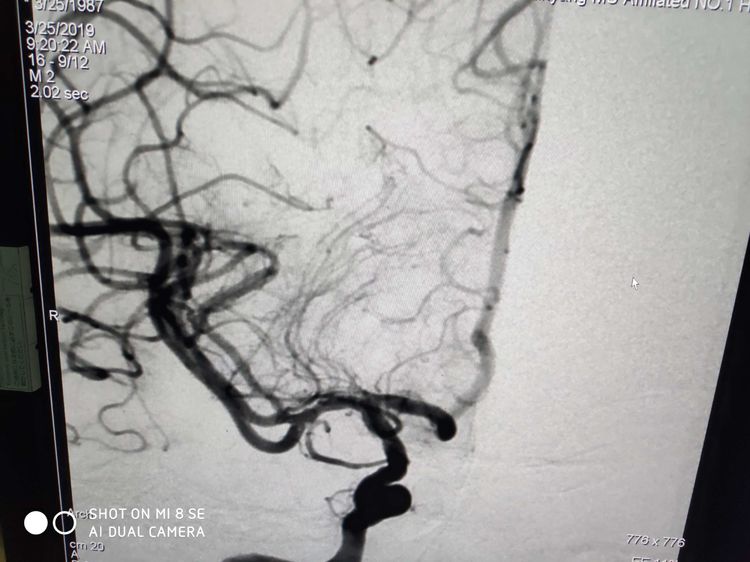

术中:右侧大脑中动脉闭塞。

立即给予取栓支架植入,拉出血栓。见下图:拉出血栓物质。